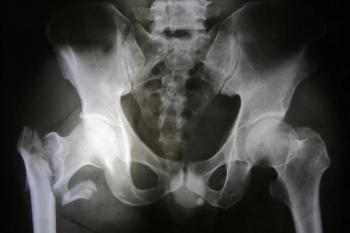

Which additional bone traits, besides bone mineral density, can be used to determine fracture risk? Authors of a new study sought to find out.

A patient's genetic predisposition to low bone mineral density can increase their risk for osteoporotic fractures, according to a new genome-wide association study.